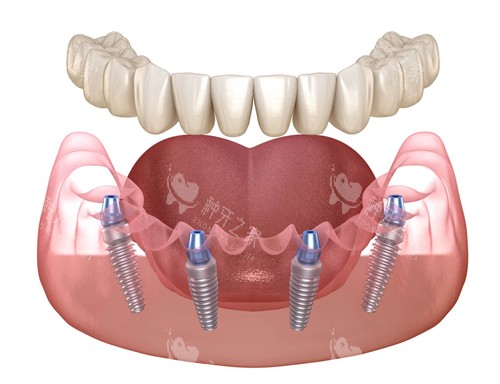

对于牙槽骨萎缩的患者,李医生也有“绝招”——斜行植入种植体。传统种植需要在牙槽骨上“打桩”,但牙槽骨萎缩重的时,桩打不稳,容易松动。而斜行植入能避开上颌窦等关键结构,用更少的骨量固定种植体。

比如半口种植,传统方法需要植入8-12颗种植体,而斜行植入只需4-6颗,费用降低三成以上,还能实现“当天种牙、当天吃饭”。一位因牙周病导致全口缺牙的王大爷,在医附大做了斜行植入种植,术后当天就用临时牙冠啃起了苹果,直夸:“这牙比真牙还结实!”